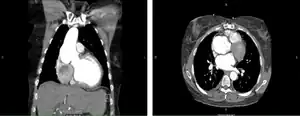

CT of the chest. Coronal (left) and axial (right) views demonstrating pathologic dilatation of the aortic root and ascending aorta. On the axial image, a dissection plane is noted in the aortic root. -

Degeneration of pulmonary autograft and aortic dissection extending into the non-coronary sinus.